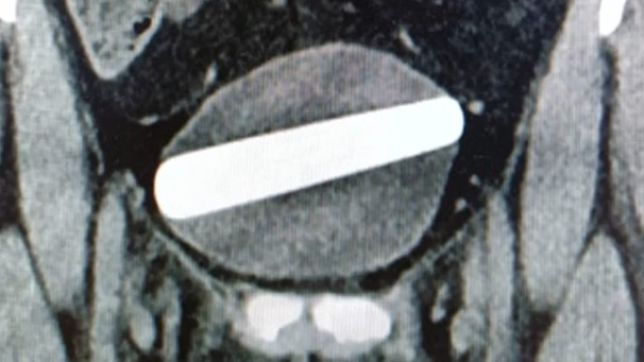

Após submeterem a turista a alguns exames de ultrassom e raio-x, descobriram que se tratava de um dildo, que estava alojado horizontalmente no interior de sua bexiga.

Segundo os médicos, uma cistoscopia foi realizada para remover o dildo de cristal por meio da uretra. Após a remoção completa do corpo estranho, a paciente recebeu alta e foi liberada a ir para casa no mesmo dia.